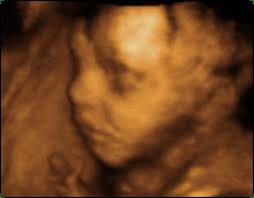

Síndrome de Patau o trisomía 13